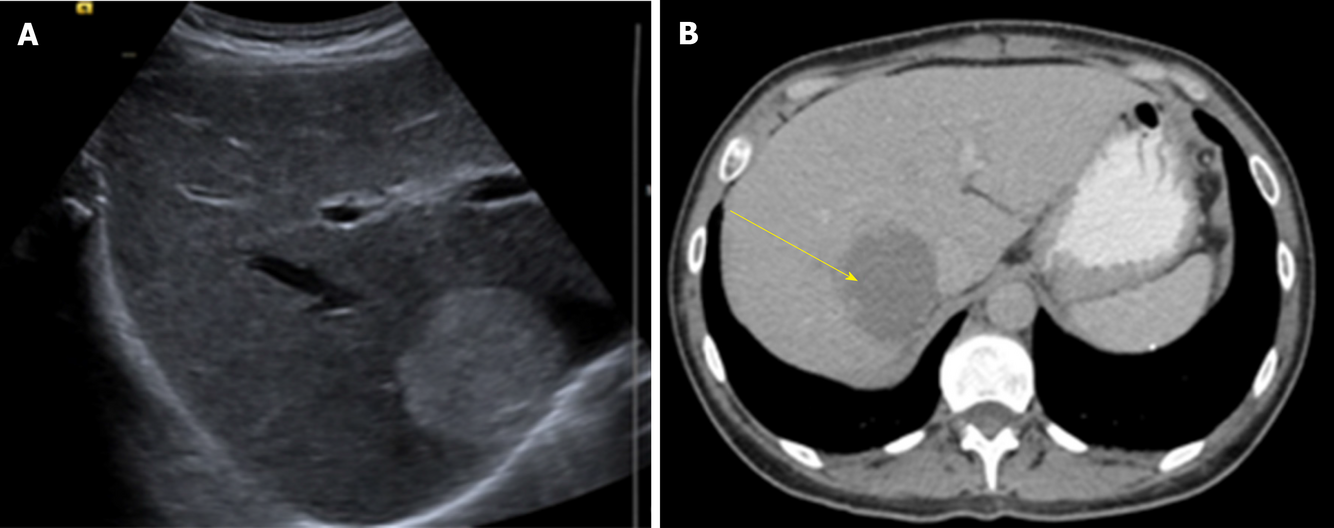

1) Cisto simples:

- Dx:

– US (S e E > 90%): anecoicos, sem septos, bordas finas, avascular ao doppler

– TC: bem delimitada, hipodenso (-10UH), sem realce em fases contrastadas

– RM: T1 baixo sinal e homogeneo; T1 C+ sem realce; T2 hipersinal